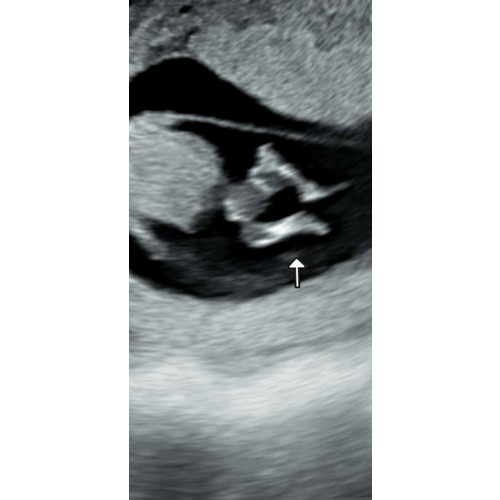

Vandaag een 11 weken echo gehad. En wat mooi om te zien dat het kindje al zo beweegt! De verloskundige kon het kindje alleen van bovenaf in beeld brengen wat een paar bijzondere kiekjes en filmpjes gaf. De mensen wie het gezien hebben zweren een jongentje te zien. De verloskundige wou nog geen uitspraak doen hierover maar vond het wel erg bijzonder. Wat vinden jullie? Het is mijn eerste kindje en heb geen ervaringen met echo foto's. Close up foto van bovenaf, buik en beentjes. (Hoofdje staat er niet op) 馃挆馃挋

Hier kun je eigenlijk nog niks op zien. De nub is pas zichtbaar met 12 weken en de geslachtsorganen zijn nog niet volledig ontwikkeld. Het is helaas nu meer gokken 馃槝